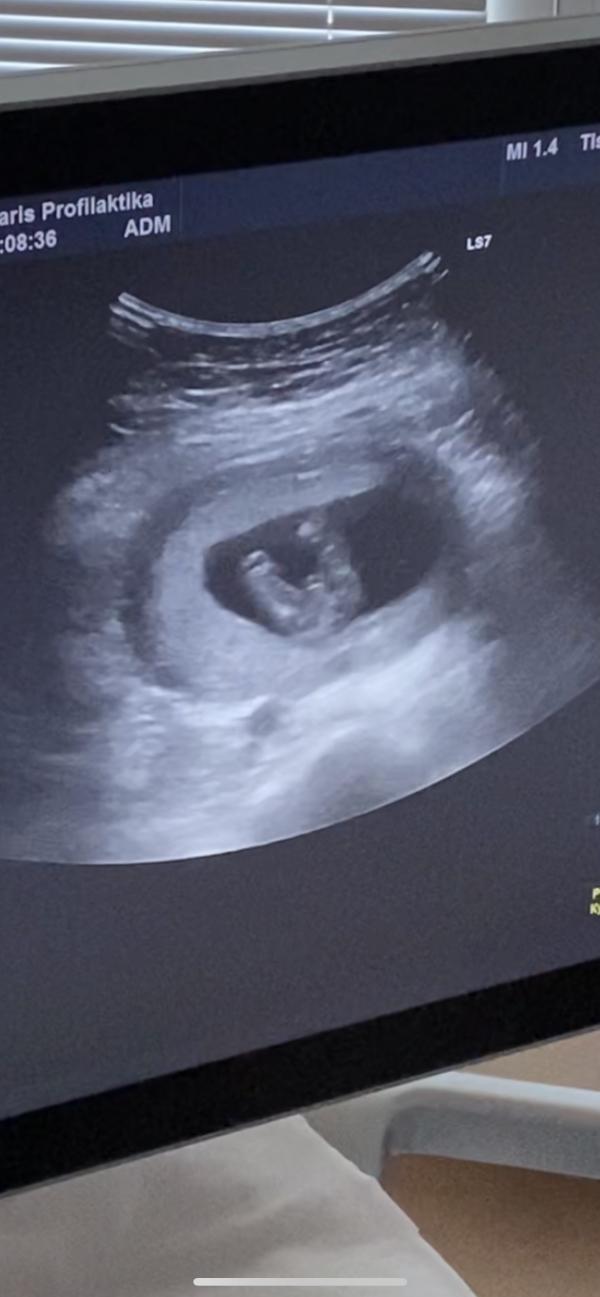

Опытные мамочки и все, кто разбираются, нужна ваша помощь☺️ Была сегодня на УЗИ, срок 14 недель. Сказали, что очень похоже на мальчика, но это неточно. Подскажите, может ли быть девочкой? Всю жизнь была уверена, что дочка будет. Заранее всем спасибо 🙏🏻

Точь в точь фотка в 12нед с дочкой. У них клитор торчит ,надо смотреть под углом а не между ног.

Я в 13 недель на скриненге смотрела на такую же фотку, только у меня девчуля, а тут явный мужичек.....,

@evstolia0788 пуповина длинная... Её не перепутать с бубенцами🤭

@gulya33, @mirpl210391, @nyushka_5, 🙏🏻 Эх, я уже поняла, но капелька надежды теплилась. Все пыталась кофейное зернышко разглядеть))

Мальчик